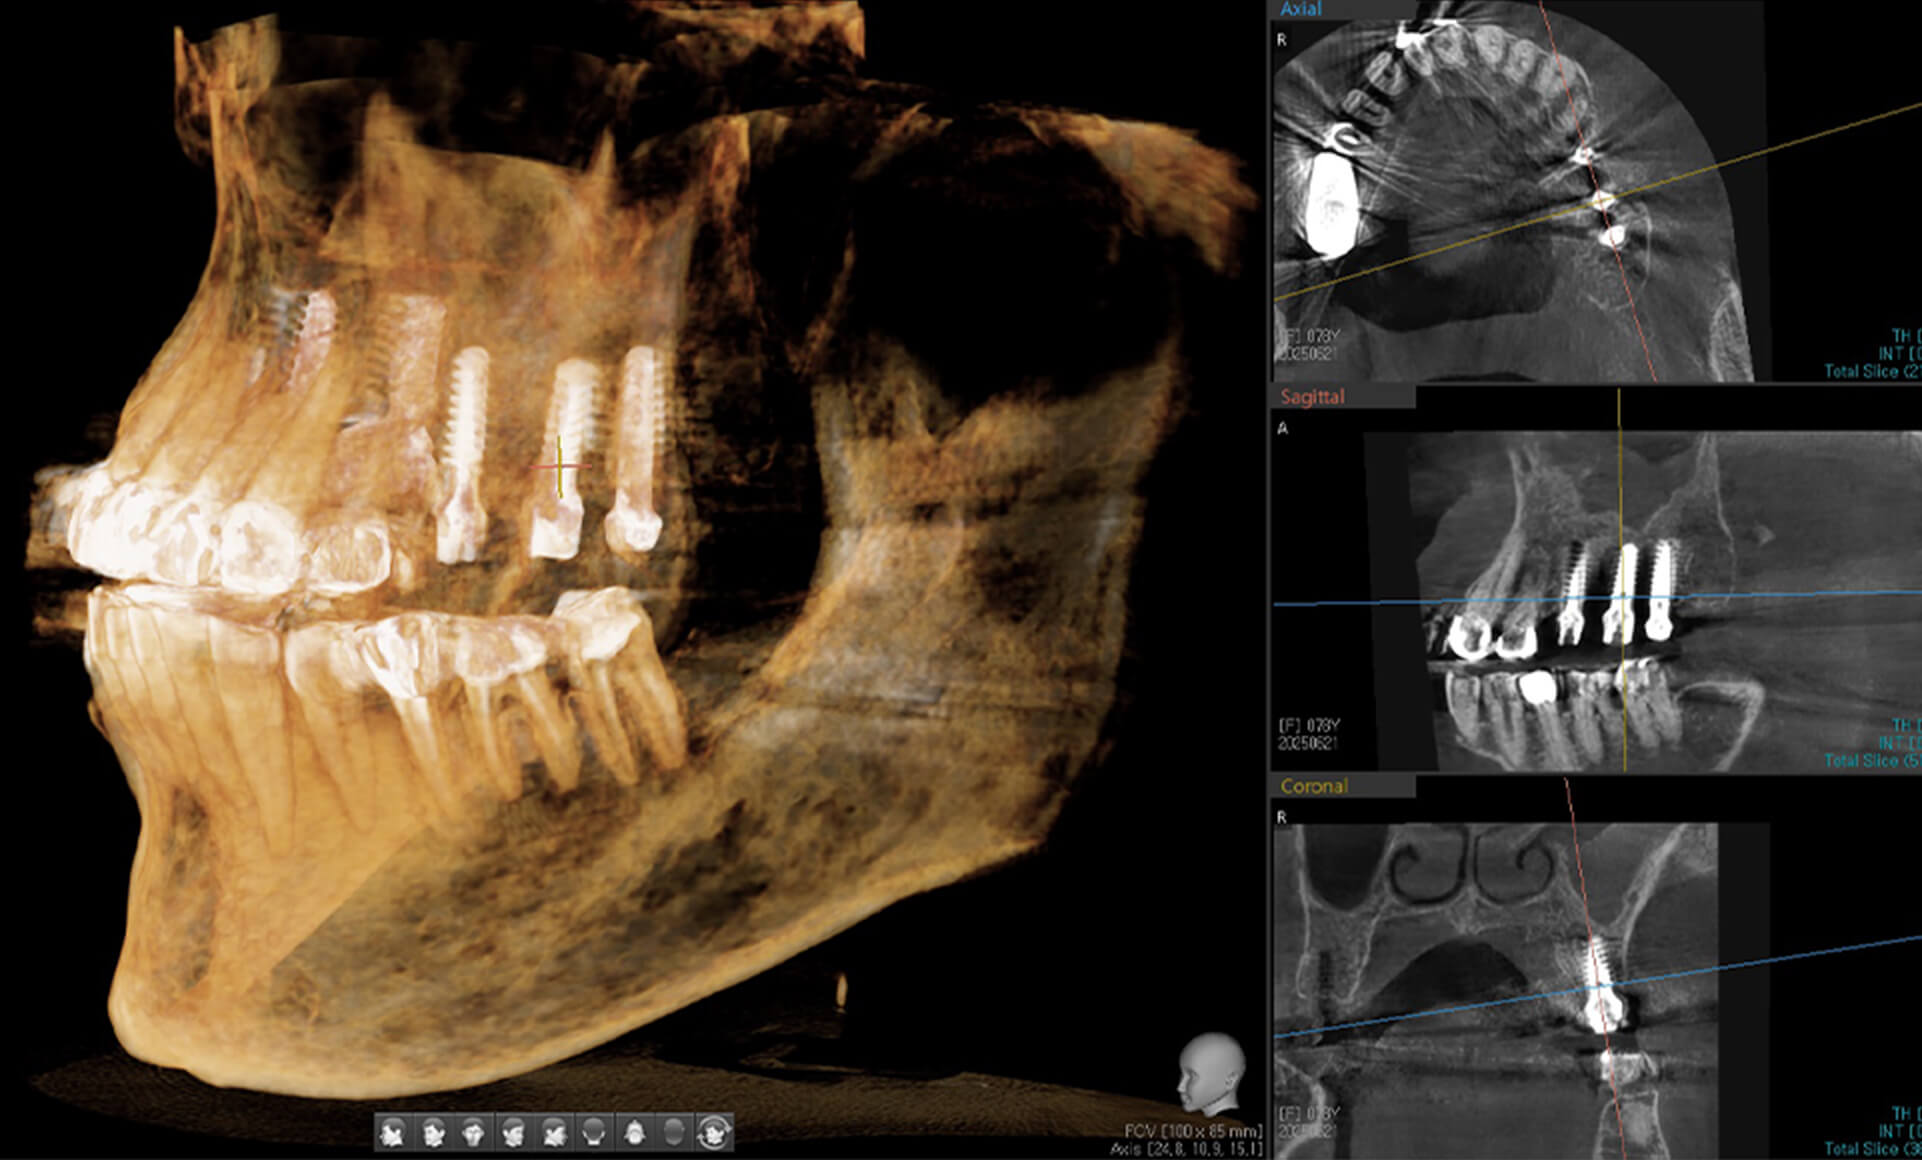

IBS 디지털가이드 (IBS Digital Guide)

IBS임플란트의 AMII GPS System은 정밀하고 안정적인 식립을 돕는 첨단 시술 보조 시스템입니다.

다양한 임상에 적용 가능하며, 편의성과 위치 수정의 용이성으로 환자와 의료진 모두에게 최적의 결과를 제공합니다.

• 정확한 식립 CT와 연동하여 사전 모의시술로 계획된 위치에 정확하게 식립